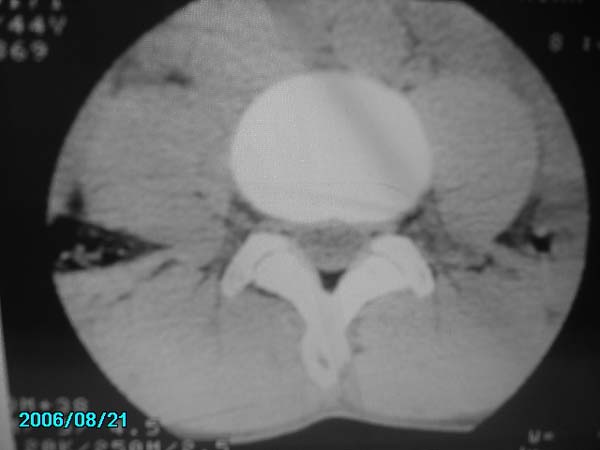

男,40岁,腰疼半年

腰4-5椎间盘后缘变平直,可考虑椎间盘轻度突出。余未见异常。

l4/5椎间盘膨出。

腰4-5椎间盘轻度突出。余未见异常。

腰椎侧弯,l4-5椎间盘膨出。

腰4-5、腰5-骶1椎间盘后缘变平直,可考虑椎间盘轻度突出。余未见异常

腰4-5椎间盘轻度突出。余未见异常

除有第3-5腰椎椎体后缘中央血管沟显示外,诸椎间盘比较正常。我也象13081830109战友那样看见了指纹,呵呵。

部分层面有轻度彭出。